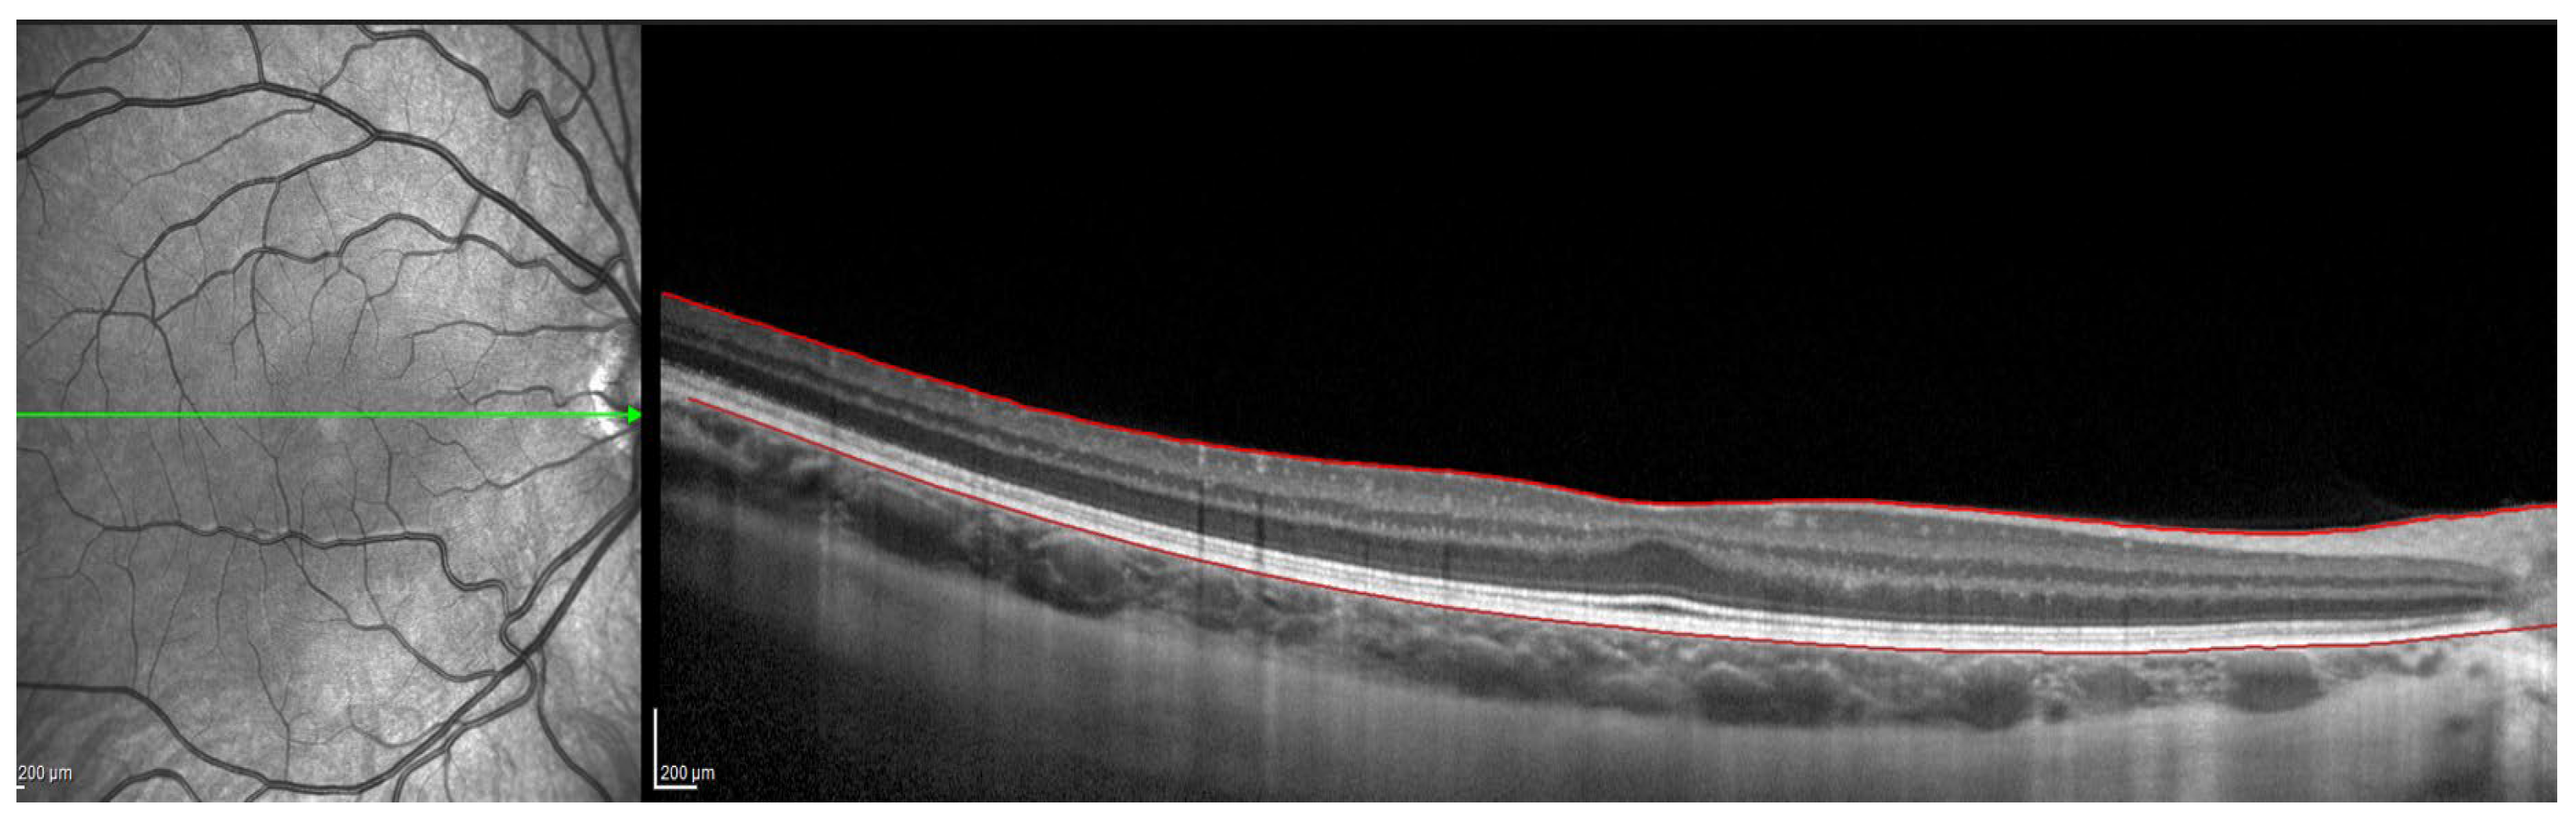

Figure 1.

OCT image with lines in red corresponding to the retinal pigment epithelium and the internal limiting membrane.

OCT Spectralis incorporates automatic segmentation software for 10 retinal layers, including total retinal thickness, nerve fiber layer, ganglion cell layer, inner plexiform and nuclear layer, outer plexiform and nuclear layer, retinal pigment epithelium, and retinal layer. This software allows the user to display all layers or select one or more layers. Once the highest-quality tomography image was selected, the researcher maintained the lines corresponding to the retinal pigment epithelium and the internal limiting membrane. This last line was used in order to be moved point by point and manually define the sclero-choroidal interface. Subsequently, the gauge provided by the instrument was used to perform the measurements. All these steps are graphically detailed in Figure 1, Figure 2, Figure 3 and Figure 4. Figure 1 shows a high-quality tomography image from a subject, with the lines corresponding to the retinal pigment epithelium (bottom red line) and the internal limiting membrane (top red line) marked in red by the automatic segmentation software.